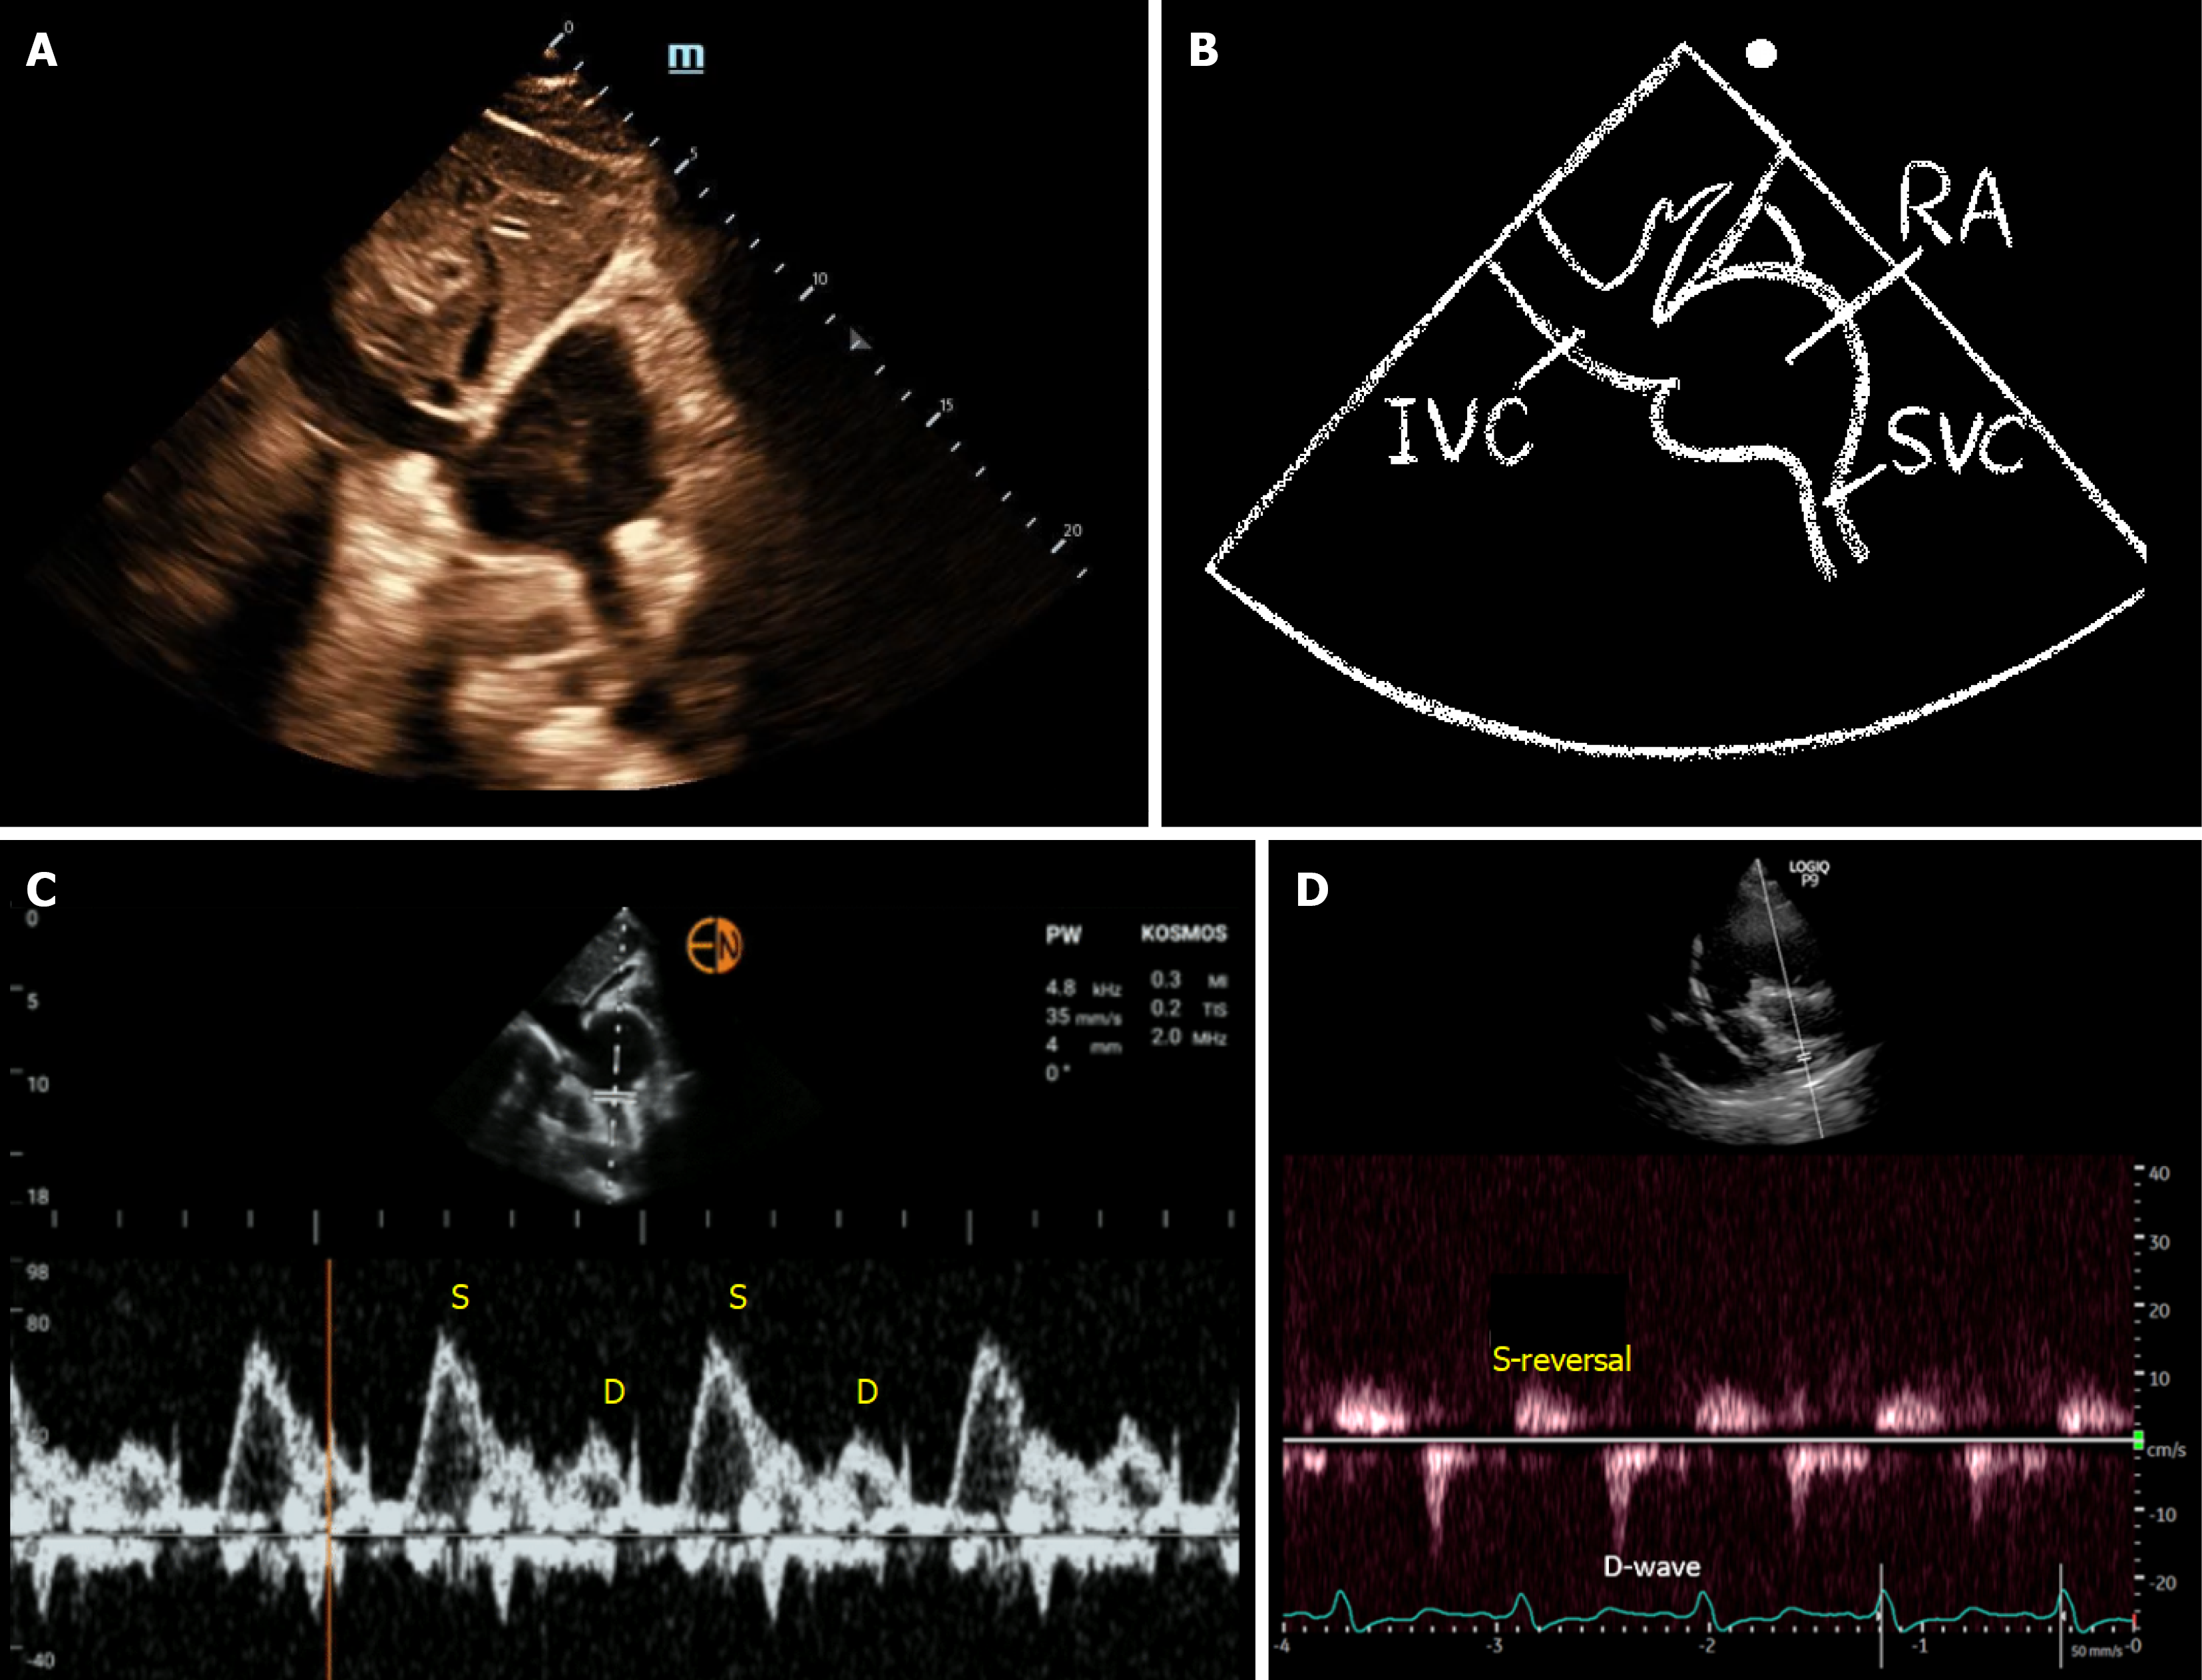

Figure 1 Venous excess ultrasound grading system.

VExUS: Venous excess ultrasound; IVC: Inferior vena cava; S: Systolic wave; D: Diastolic wave. Figure reused with permission from NephroPOCUS.com. Available from: https://nephropocus.com/2021/10/05/vexus-flash-cards/.

Figure 4 Superior vena cava Doppler.

A and B: Subcostal bicaval view with corresponding illustration; C and D: Panel C shows a normal superior vena cava Doppler waveform obtained from the bicaval view with a systolic wave greater than the diastolic wave. Panel D demonstrates a severely abnormal pattern with systolic wave reversal. The tracing in panel D was obtained from a modified parasternal view, which often results in suboptimal Doppler angle and consequently lower recorded flow velocities. IVC: Inferior vena cava; RA: Right atrium; SVC: Superior vena cava; S: Systolic; D: Diastolic.